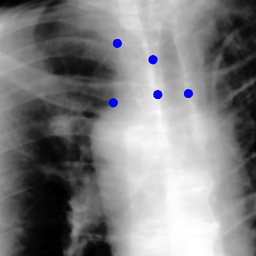

The dataset we use in the experiments is a cone-beam CT (CBCT) dataset captured for radiation therapy. The dataset contains 340 raw CBCT scans with each has 780 X-ray images. Each X-ray image comes with a geometry file that provides the registration ground truth as well as the information to reconstruct the CBCT volume. Each CBCT volume is reconstructed from the 780 X-ray images, and in total, we have 340 CBCT volumes (one for each CBCT scan). We use 300 scans for training and validation, and 40 scans for testing. The size of the CBCT volumes is 448×448×768448448768448\times 448\times 768 with 0.5 mm voxel spacing, and the size of the X-ray images is 512×512512512512\times 512 with 0.388 mm pixel spacing. During the experiments, the CBCT volumes are treated as the 3D pre-intervention data, and the corresponding X-ray images are treated as the 2D intra-intervention data. Sample X-ray images from our dataset are shown in Figure. Note that unlike many existing approaches [15, 17, 25] that evaluate their methods on small datasets (typically about 10 scans) which are captured under relatively ideal scenarios, we use a significantly larger dataset with complex clinical settings, e.g., diverse field-of-views, surgical instruments/implants, various image contrast and quality, etc.

We consider two common views during the experiment: the anterior-posterior view and the lateral view. Hence, only X-rays that are close to (±5°plus-or-minus5°\pm 5\degree) these views are used for training and testing. Note that this selection does not tightly constrain the diversity of the X-rays as the patient may be subject to movements with regard to the operating bed. To train the proposed method, X-ray and DRR pairs are selected and generated with a maximum of 10°10°10\degree rotation offset and 202020 mm translation offset. We first invert all the raw X-ray images and then apply histogram equalization to both the inverted X-ray images and DRRs to facilitate the similarity measurement. For each of the scan, we also annotate their landmarks on the reconstructed CBCT volume for further evaluation.

Refer to caption

Figure 6: Sample raw X-ray images of our dataset.